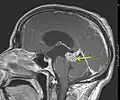

En début d'évolution, l'imagerie montre une tumeur isodense au scanner, d'où l'intérêt de l'IRM, plus sensible au dépistage de cette tumeur peu vascularisée. Lors de l'évolution, le scanner montre une tumeur hypodense, ne prenant généralement pas le produit de contraste. Il n'est pas retrouvé d'effet de masse puisque la tumeur est infiltrante.

Une biopsie peut être envisagée pour confirmer le diagnostic d'astrocytome, préciser le grade histologique.